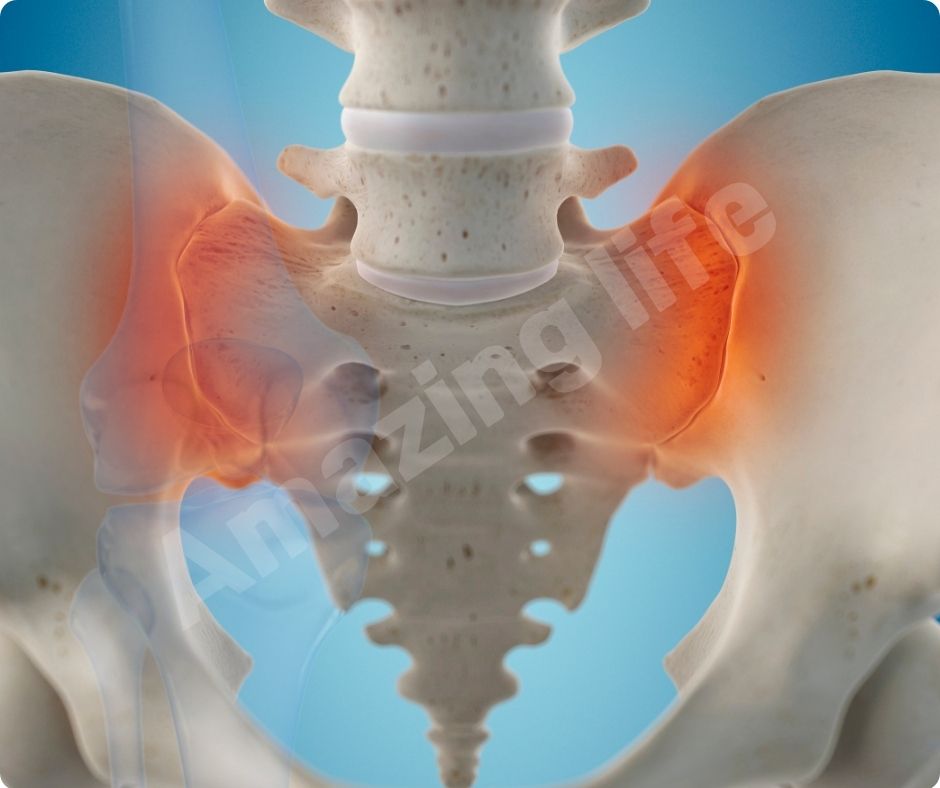

염증 감소

글루코사민의 효능은 염증을 감소시키는 데도 효과적입니다. 관절염은 염증으로 인해 발생하는 경우가 많으므로, 글루코사민을 통해 염증을 줄이면 관절염 증상을 완화할 수 있습니다. 이는 자연적인 방법으로 관절 건강을 유지하는 데 유용합니다.